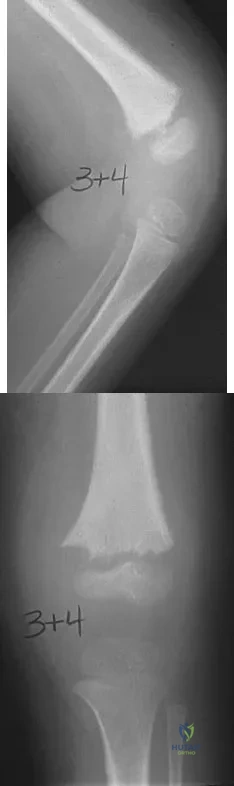

Figures 32a and 32b show the AP and lateral radiographs of an 11-year-old boy who has a severe limp, a fever, and swelling and tenderness of the thigh. Aspiration of the bone reveals purulent material. The patient has most likely been symptomatic for